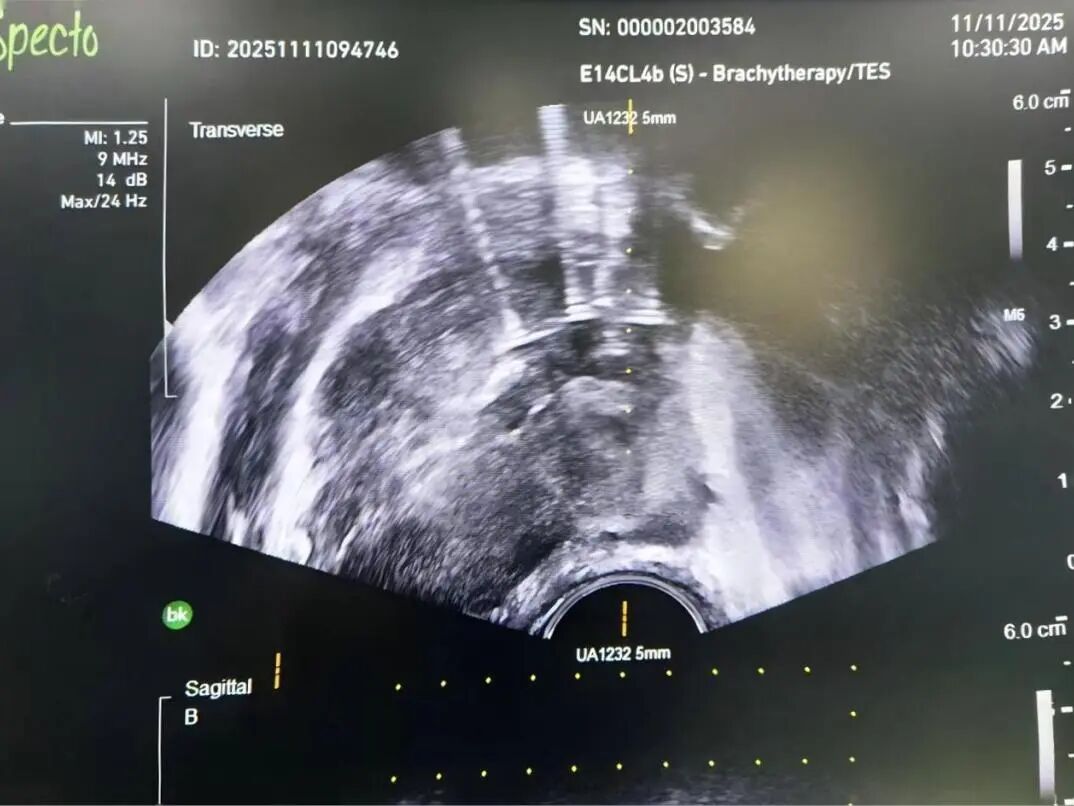

前列腺恶性肿瘤 是男性常见的泌尿系统肿瘤之一 当病情步入中晚期 治疗的关键在于结合系统治疗 一项能够直击病灶 持续作用的微创技术 为综合治疗拓展了新的可能 近日,贵州航天医院泌尿外科团队成功开展一例超声引导下经会阴前列腺碘125粒子植入术,为患者制定了个体化治疗方案。 案例分享 近期,一位年近八旬的男性患者因左侧髋部不适伴下肢放射痛前来就诊,初步检查提示可能存在前列腺肿瘤伴骨转移,为进一步明确诊断,患者随即转入泌尿外科诊治。泌尿外科为患者完善了相关检查,随后在超声引导下实施了经会阴前列腺穿刺活检,结合磁共振(MRI)影像与病理结果,最终明确诊断为前列腺腺癌(T4N0M1)。 考虑到患者年纪较大、身体状况比较弱,加上肿瘤已是晚期,已不适合创伤较大的前列腺癌根治性切除手术。为提供更佳的治疗方案,泌尿外科组织呼吸与危重症医学科肿瘤病区的专家进行了多学科讨论评估,征得家属同意后,定了一个分两步走的治疗方案:先实施前列腺肿瘤碘125粒子植入微创手术(把带辐射的小粒子放到患处杀灭肿瘤细胞),手术后,再配合药物(内分泌治疗)来控制病情。手术过程顺利,患者恢复良好,目前已出院并定期随访中。 术后植入粒子影像 我院多学科诊疗(MDT)已成为应对复杂疾病的常规模式,通过整合多学科的资源与优势,汇聚外科、内科、肿瘤、微创介入、影像、检验等多学科专家进行会诊,突出个体化治疗和综合全面治疗,提高诊疗效率和精准性,避免患者在多个科室间反复挂号奔波,缩短诊疗等待时间,让广大肿瘤、疑难重症患者享受到更加优质、专业、“一站式”的诊疗服务。 什么是放射性粒子植入技术 放射治疗是肿瘤治疗的常见手段之一,主要包括外照射与近距离放射治疗,碘125粒子植入属于持续低剂量率近距离放疗的一种,将微型放射性粒子永久植入前列腺组织内,通过持续释放射线作用于肿瘤区域,治疗前需通过影像学检查精确评估前列腺形态、体积,并制定个体化的剂量分布计划,术中在超声实时引导下植入粒子,以便根据实际情况调整进针路径与剂量分布,尽量使射线覆盖前列腺及其周边一定范围。该技术通常适用于部分局部进展性或转移性前列腺肿瘤患者,可作为综合治疗策略中的一环。 放射性粒子植入技术优势 1.能够把粒子准确植入肿瘤中,定位精准,靶向性强,高度适形。 2.肿瘤接受的放射剂量明显增加,而不增加正常组织的剂量。 3.持续低剂量率放射,能对不同分裂周期的肿瘤细胞进行不间断照射,提高了放射敏感性,累计射线剂量可达外放疗的2~3倍,有较高的放射生物效应。 4.粒子植入的部位肿瘤组织可被杀灭,距粒子1cm以外的正常组织几乎不受损伤,能有效降低正常组织受照剂量,正常组织损伤小,几乎不造成白细胞下降、骨髓抑制、胃肠道反应、脱发等副作用,病人无痛苦。 5.粒子外壳为钛合金,与人体有很好的组织相容性,不会产生排异及放射泄漏。 6.与其他的肿瘤治疗方法相比,创伤小、生活质量高、住院时间短。 7.能与手术、化疗及外放疗配合互补提高疗效。 注:本文仅为医疗技术介绍,具体治疗方案请务必咨询临床医生,并结合患者个体情况制定。部分图片来源于网络,如有侵权,请联系删除。 贵州航天医院 泌尿外科专家简介 石 英 泌尿外科党支部书记、主任,主任医师 中国医师协会泌尿外科分会感染协作组委员,奥林巴斯泌尿系软镜西南区专家组成员,西南地区第一批输尿管软镜专家组成员,贵州省医学会泌尿外科分会委员,贵州省性学会理事,贵州省性学会常务委员,贵州省泌尿外科专业医疗质量控制中心专家委员会委员。 从事泌尿外科专业近30年,熟练掌握泌尿系各类疾病的诊治,具有丰富的临床经验,擅长泌尿系结石、腹膜后肿瘤及泌尿系肿瘤的手术治疗,对泌尿系感染、泌尿系结核、尿源性脓毒血症的救治有独到的见解及抢救经验,在贵州省率先引入输尿管软镜技术,同时在男科领域,对男性阳痿、早泄及前列腺疾病有很深的研究。 李国成 泌尿外科副主任,副主任医师 中国人体健康科技促进会男科学专业委员会委员,贵州省性学会泌尿外科分会委员,贵州省医学会男科学分会委员,遵义市医学会男科学分会副主任委员兼秘书长,遵义市医学会泌尿外科分会常务委员,贵州航天医院男科带头人。 从事泌尿外科及男科工作10余年,曾多次前往上海交通大学附属第一人民医院、中国中医科学院西苑医院进修学习男科;擅长性功能障碍的诊治、男性整形手术、前列腺增生激光手术、显微手术等。 李 凯 中共党员,泌尿外科副主任医师 贵州航天医院肿瘤腔镜组带头人,擅长肾癌根治术、输尿管癌根治术、膀胱及前列腺癌根治术、腹腔镜输尿管狭窄切除吻合术、输尿管切开取石术等手术,在遵义市率先开展泌尿系结核后膀胱挛缩全腹腔镜下膀胱扩大术。 贵州省医学会泌尿外科分会青年委员,遵义市医学会男科分会常务委员,遵义市医学会泌尿外科分会常务委员。 贵州航天医院泌尿外科简介 • ✦ 基本情况 ✦ • 贵州航天医院泌尿外科创建于20世纪60年代,经过几代人的努力,微创与内镜手术占比达90%以上,科室亚专业框架完善。是贵州省临床重点专科建设单位、北京清华长庚医院李建新教授团队诊疗及会诊中心、北京医学会尿路修复与重建诊疗及会诊中心、上海公济泌尿外科集团遵义中心、上海援黔专家李铮教授男科工作室、贵州省泌尿外科质量控制专家委员单位。 • ✦ 专科特色技术 ✦ • (一)泌尿系结石内镜碎石技术 泌尿系结石微创治疗领域方面是贵州省首家引进科医人钬激光碎石技术科室,在遵义地区率先掌握输尿管硬镜、软性镜,经皮肾镜钬激光碎石技术。目前是北京清华长庚医院泌尿外科“手把手”经皮肾镜碎石技术培训基地、贵州省输尿管软镜培训基地。 1.负压吸引可弯曲软镜鞘电子软镜碎石术 2.标准与超微通道相结合的经皮肾镜碎石取石术 (二)微创腹腔镜技术 泌尿外科腹腔镜技术师承于浙江省人民医院、北大、北京解放军总医院。目前采用经腹、经后腹双入路法的腹腔镜技术完成肾部分切除、肾切除、肾输尿管全长切除、肾盂输尿管成形、输尿管狭窄吻合、膀胱翻瓣等手术。在遵义地区率先掌握腹腔镜下膀胱癌根治术、腹腔镜下前列腺癌根治术。 (三)男科、盆底技术临床应用 遵义地区男科分会主委单位,是贵州省首家引进尿动力学检查并取得了全国资质认证科室,也是贵州省首家进行RigiScan检查的单位。在遵义地区率先掌握显微取精子技术以及显微镜下治疗精索静脉曲张、显微镜下输精管吻合、输精管附睾吻合技术。率先采用前列腺激光剜除术治疗前列腺增生症。在陆军军医大学西南医院泌尿外科主任沈文浩教授指导下,完成遵义市首例神经源性膀胱骶神经调节刺激器置入术。 • ✦ 诊疗范围 ✦ • 诊疗范围(除外肾移植、癌栓):泌尿系结石、泌尿系肿瘤、肾上腺疾病、肾积水、前列腺增生、男性生殖器功能障碍(精索静脉曲张、生殖道感染、输精管梗阻等)、盆底功能障碍性疾病(膀胱脱垂、排尿功能异常、尿失禁)、泌尿生殖系畸形。 泌尿外科拥有独立门诊治疗室、日间手术室、尿动力学检查室、精液分析检查室、男性勃起功能检查及治疗室、ESWL治疗室、结石分析检查室。